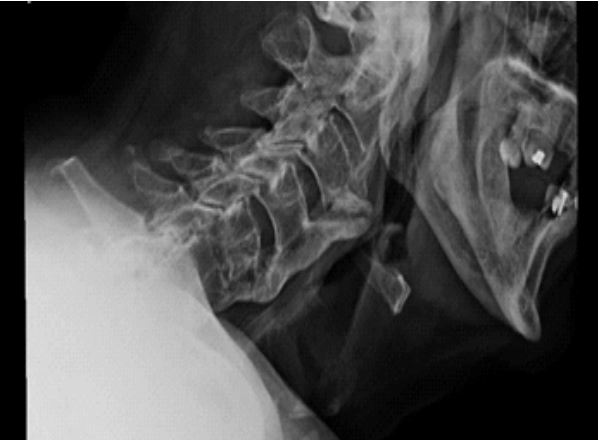

Due to the lack of improvement in swallowing function, a fiberoptic endoscopic evaluation was performed (Figure 1): a severe anteriorization of the posterior pharyngeal wall was coming into contact with the epiglottis with consequent reduction of the lumen and marked stagnation of secretions. To investigate the causes of pharyngeal stenosis, an x-ray of the cervical spine was performed (Figure 2). The x-ray showed anterior cervical osteophytes at C3, C4, C5 and C6; therefore, computed tomography was carried out (Figure 3). Osteophytic alterations with a tendency towards bridging fusion in the C2-C5 tract was described. Coarse ossification of the anterior longitudinal ligament with evidence of a spur shaping an acute angle at the level of the epiglottis, significantly imprinted the posterior wall of the hypopharynx and determined a clear focal reduction in the calibre of the lumen. The diagnosis of ankylosing spondylitis, infection and malignancy were ruled out and Forestier Disease was confirmed.

Figure 2: Cervical X ray.